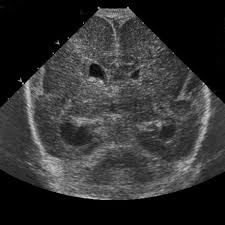

Lissencephaly, which literally means smooth brain, is a rare brain formation disorder caused by defective neuronal migration during the 12th to 24th weeks of gestation resulting in a lack of development of brain folds (gyri) and grooves (sulci). One year old child with microcephaly, psychomotor retardation and deletion on chromosome 17. It is a condition that results from the defective migration of. Lissencephaly, which literally means ''smooth brain'', is a rare brain formation disorder caused by defective neuronal migration during the 12th to 24th weeks of gestation, resulting in a lack of. • very few or no gyri are lissencephaly. Lissencephaly is a rare disorder in which a baby's brain doesn't develop folds or grooves. Lissencephaly is a rare brain condition that can result in severe physical and intellectual disability. Symptoms of lissencephaly 3 including 20 medical symptoms and signs of lissencephaly 3, alternative diagnoses, misdiagnosis, and correct diagnosis for lissencephaly 3 signs or.

Jump to navigation jump to search. Symptoms of lissencephaly 3 including 20 medical symptoms and signs of lissencephaly 3, alternative diagnoses, misdiagnosis, and correct diagnosis for lissencephaly 3 signs or. Hypoplasia of pons & cerebellum. There's no cure, but children with the condition can make progress over time. Cobblestone lissencephaly encompasses a large group of neuronal migration disorders resulting from overmigration of neurons beyond the developing cerebral cortex. View lissencephaly research papers on academia.edu for free. Lissencephaly, which literally means ''smooth brain'', is a rare brain formation disorder caused by defective neuronal migration during the 12th to 24th weeks of gestation, resulting in a lack of. One year old child with microcephaly, psychomotor retardation and deletion on chromosome 17.

One year old child with microcephaly, psychomotor retardation and deletion on chromosome 17 lisse. Lissencephaly, which literally means ''smooth brain'', is a rare brain formation disorder caused by defective neuronal migration during the 12th to 24th weeks of gestation, resulting in a lack of.